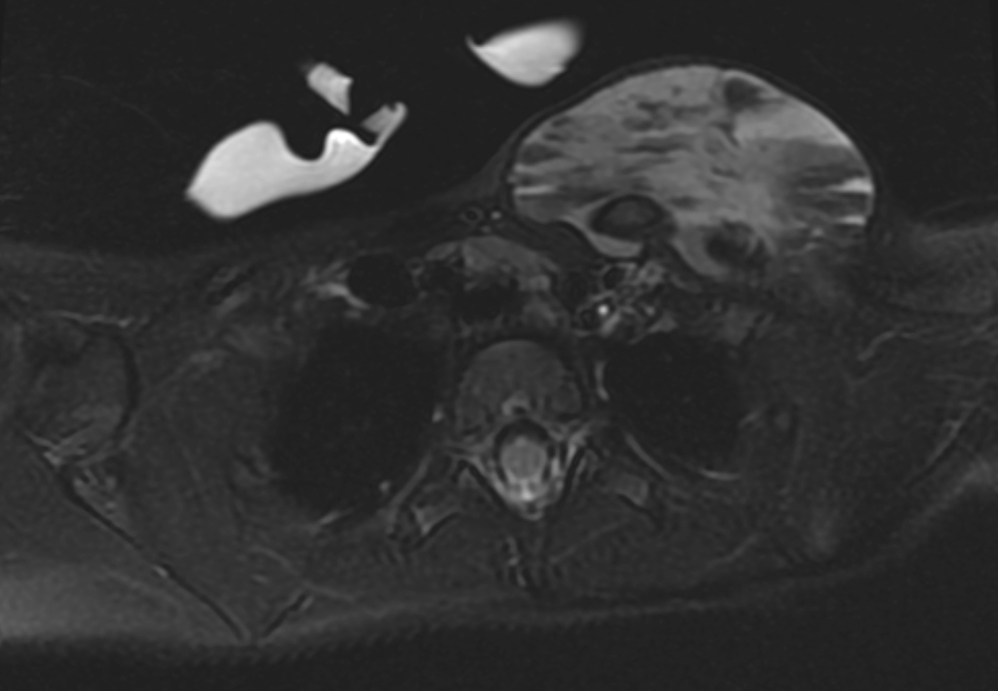

Almost everybody who has a vascular malformation will need imaging of some sort to evaluate it. Imaging helps us to know what structures are involved and how deep the lesion is. It could be what we call a “tip of the iceberg” lesion where only a little bit is visible on the skin surface but it goes deeper and involves muscles, bone or something else. Imaging, which is almost always magnetic resonance imaging (MRI), allows us to look at the lesion in question and understand how it relates to the other tissues. Other modalities are effective, too, such as computed tomography (CT) when bones are involved, angiography when blood vessels are involved, and ultrasound for other situations.